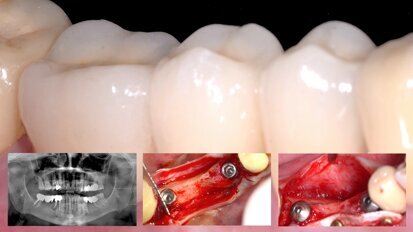

Tecnología para el éxito en cirugía bucal e implantología

La Sociedad Española de Cirugía Bucal celebró en Sierra Nevada la VI Reunión de Invierno SECIB los días 1 y 2 de marzo. La gestión y las nuevas ...